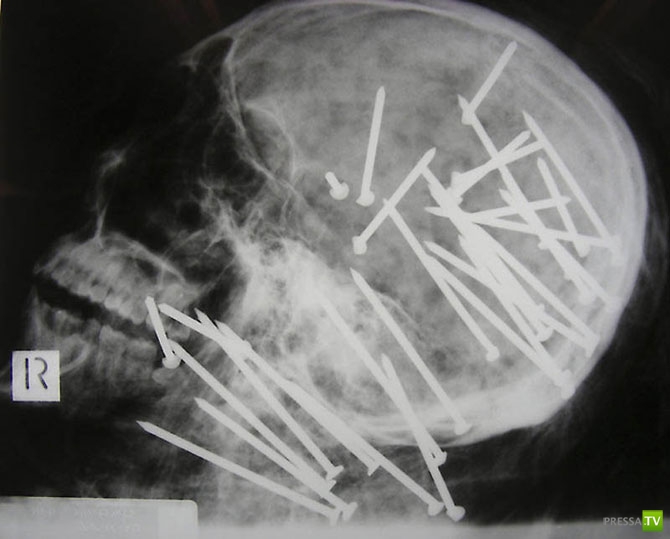

Череп человека, которому в голову выстрелили пневматическим молотком.